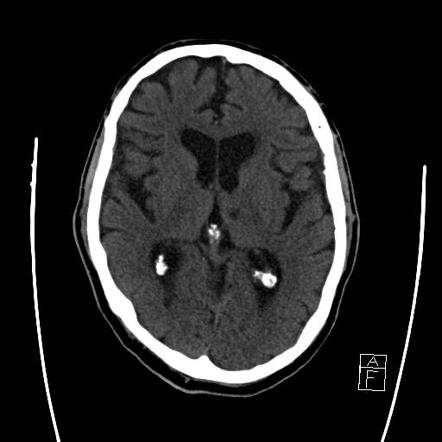

Chụp cắt lớp vi tính (CT Scan), chụp cộng hưởng từ (MRI), chụp X-quang, điện tâm đồ (EKG), siêu âm.

Click vào ảnh để xem 5 hình ảnh minh họa